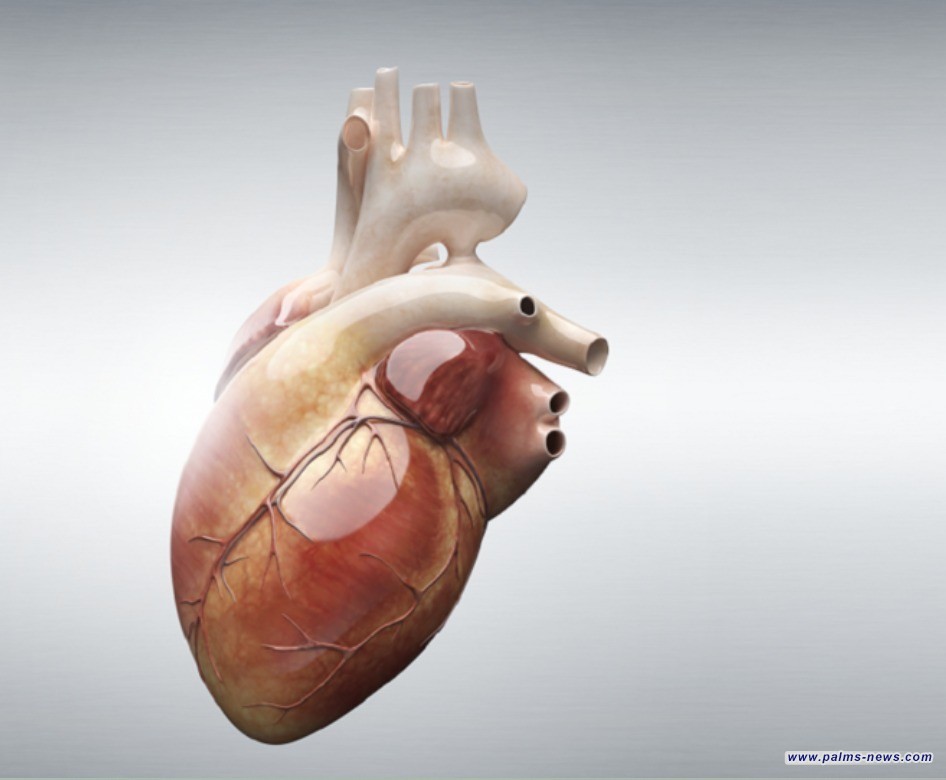

ثورة طبية.. ابتكار أصغر جهاز لتنظيم ضربات القلب في العالم

طوّر فريق من المهندسين في جامعة نورث وسترن الأمريكية جهاز تنظيم ضربات قلب متطورا فائق الصغر، يمكن حقنه عبر محقنة قابلة للذوبان دون الحاجة إلى تدخل جراحي.

ويتميز هذا الجهاز، المصمم لتنظيم ضربات القلب مؤقتا، بكونه أقل تدخلا من الأجهزة التقليدية، ما يجعله مثاليا للأطفال الرضع الذين يعانون من عيوب خلقية في القلب.

ويبلغ حجم جهاز تنظيم ضربات القلب أقل من حبة أرز، ويتم تشغيله من خلال جهاز لاسلكي مرن يثبت على صدر المريض (يستخدم ضوء الأشعة تحت الحمراء لاختراق الجسم بأمان)، الذي يراقب نبضات القلب، وعند رصد أي اضطراب، يصدر نبضة ضوئية تخترق الجلد لتنشيط جهاز تنظيم ضربات القلب المزروع، ما يساعد على استعادة الإيقاع القلبي الطبيعي تلقائيا بكفاءة، دون الحاجة إلى أسلاك أو بطاريات تقليدية.

ولمواجهة تحدي تصغير حجم الجهاز، أعاد فريق البحث تصميم نظام الطاقة، مستبدلا البطارية التقليدية بخلية فولتية صغيرة تولد الكهرباء عبر تفاعل كيميائي بين قطبين معدنيين مختلفين والسوائل الحيوية في الجسم، ما يجعل الجهاز صغيرا جدا وقابلا للذوبان بعد أداء وظيفته دون الحاجة إلى جراحة إضافية لإزالته. وعند زرع الجهاز، تعمل السوائل كإلكتروليت موصل (مادة تحتوي على أيونات حرة)، ما يسمح له بإنتاج النبضات الكهربائية اللازمة لتحفيز القلب.

وصرح جون أ. روجرز، رائد الإلكترونيات الحيوية في جامعة نورث وسترن وقائد فريق التطوير: "لقد ابتكرنا، على حد علمنا، أصغر جهاز تنظيم ضربات قلب في العالم".

وأوضح إيغور إيفيموف، المشارك في قيادة الدراسة: "كان هدفنا الأساسي هو الأطفال، حيث يولد حوالي 1% منهم بعيوب خلقية في القلب، سواء في دول غنية أو محدودة الموارد. الآن، يمكننا تثبيت هذا الجهاز مباشرة على القلب، وتحفيزه بجهاز مرن يُرتدى على الجلد، دون الحاجة إلى جراحة لإزالته".

وبفضل حجمه الصغير، يمكن زرع عدة أجهزة في مواقع مختلفة حول القلب وتشغيلها بشكل مستقل عبر ألوان ضوئية مختلفة، ما يفتح المجال لعلاج اضطرابات نظم القلب المتنوعة. كما تحمل هذه التقنية إمكانيات واسعة في مجالات الطب الحيوي، مثل تسريع التئام الأعصاب والعظام وعلاج الجروح وتخفيف الألم.